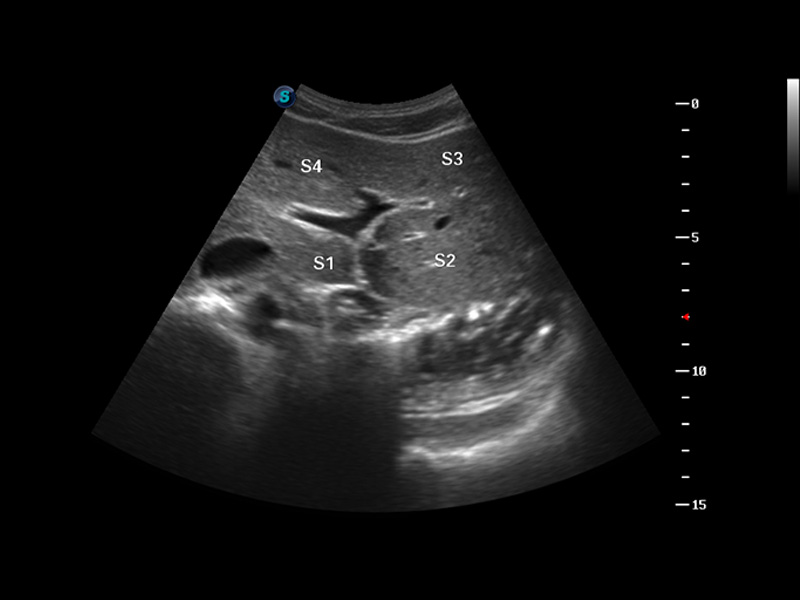

S8 EXP便携式彩色多普勒超声诊断仪是米兰官方网站研发的高端全身应用型便携彩超。高通道的VIS平台融合可视化(Visual)、智能化(Intelligent)和人性化(Smart)的特点,配以米兰官方网站自主研发生产的探头大家族,使您能够快速、准确的获得病人信息,提高工作效率的同时减轻疲劳。

μ-Scan微米成像

谐波成像

空间复合成像

3D/4D成像